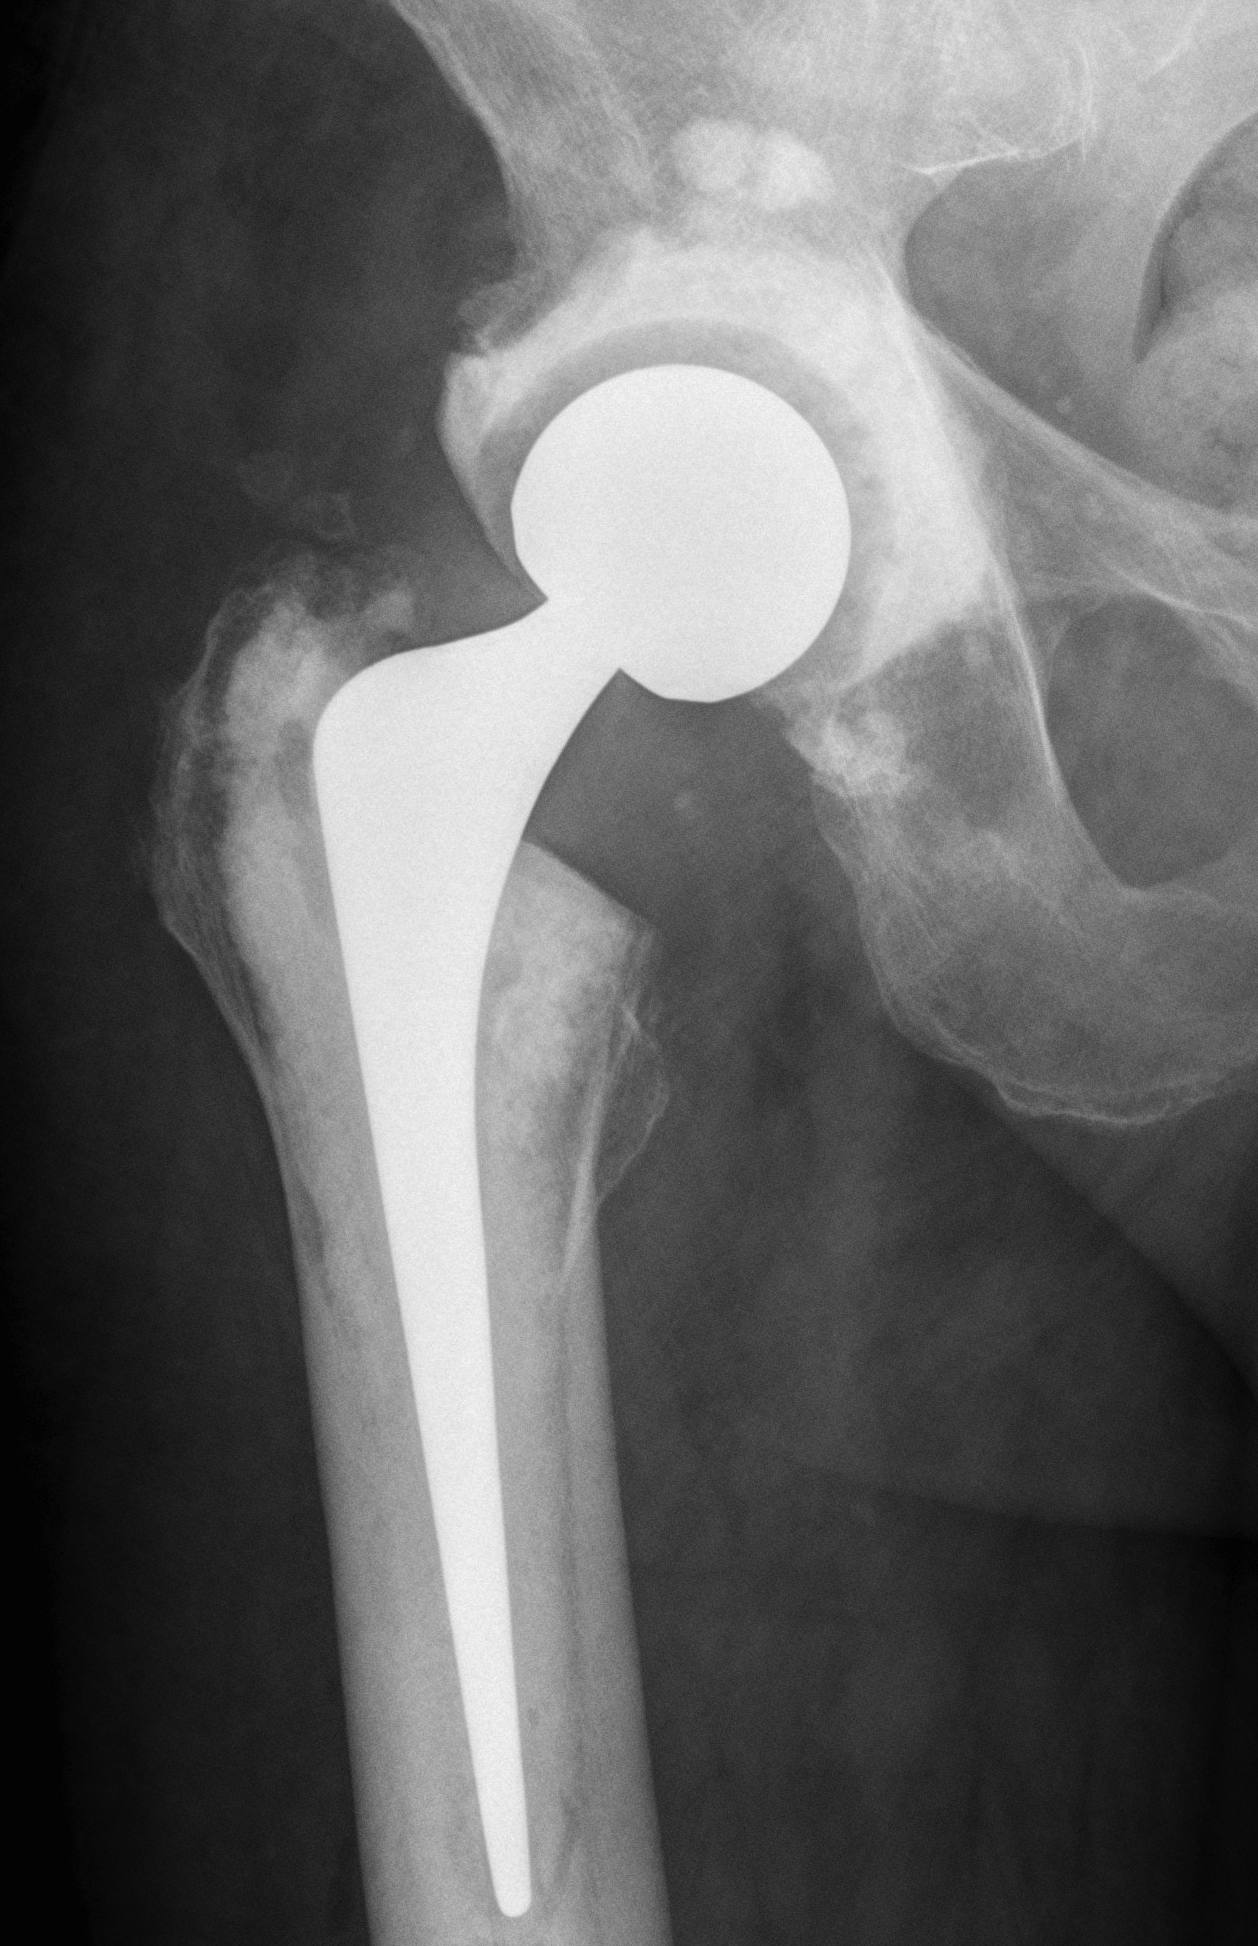

One-Stage Revision

Concept

Remove prosthesis, debride and replace at single sitting

- meticulous debridement critical

- antibiotic cement both femur and acetabulum

Technique

Debridement + removal of implants and all cement

- wash +++

- re-drape, new instruments

Implant cemented polished femur and all poly cup

- must use antibiotic cement

- guidance on antibiotic choice from multidisciplinary team (ID)

- for example add powder form vancomycin

- 2-3 gram vancomycin in each 40g packet of cement